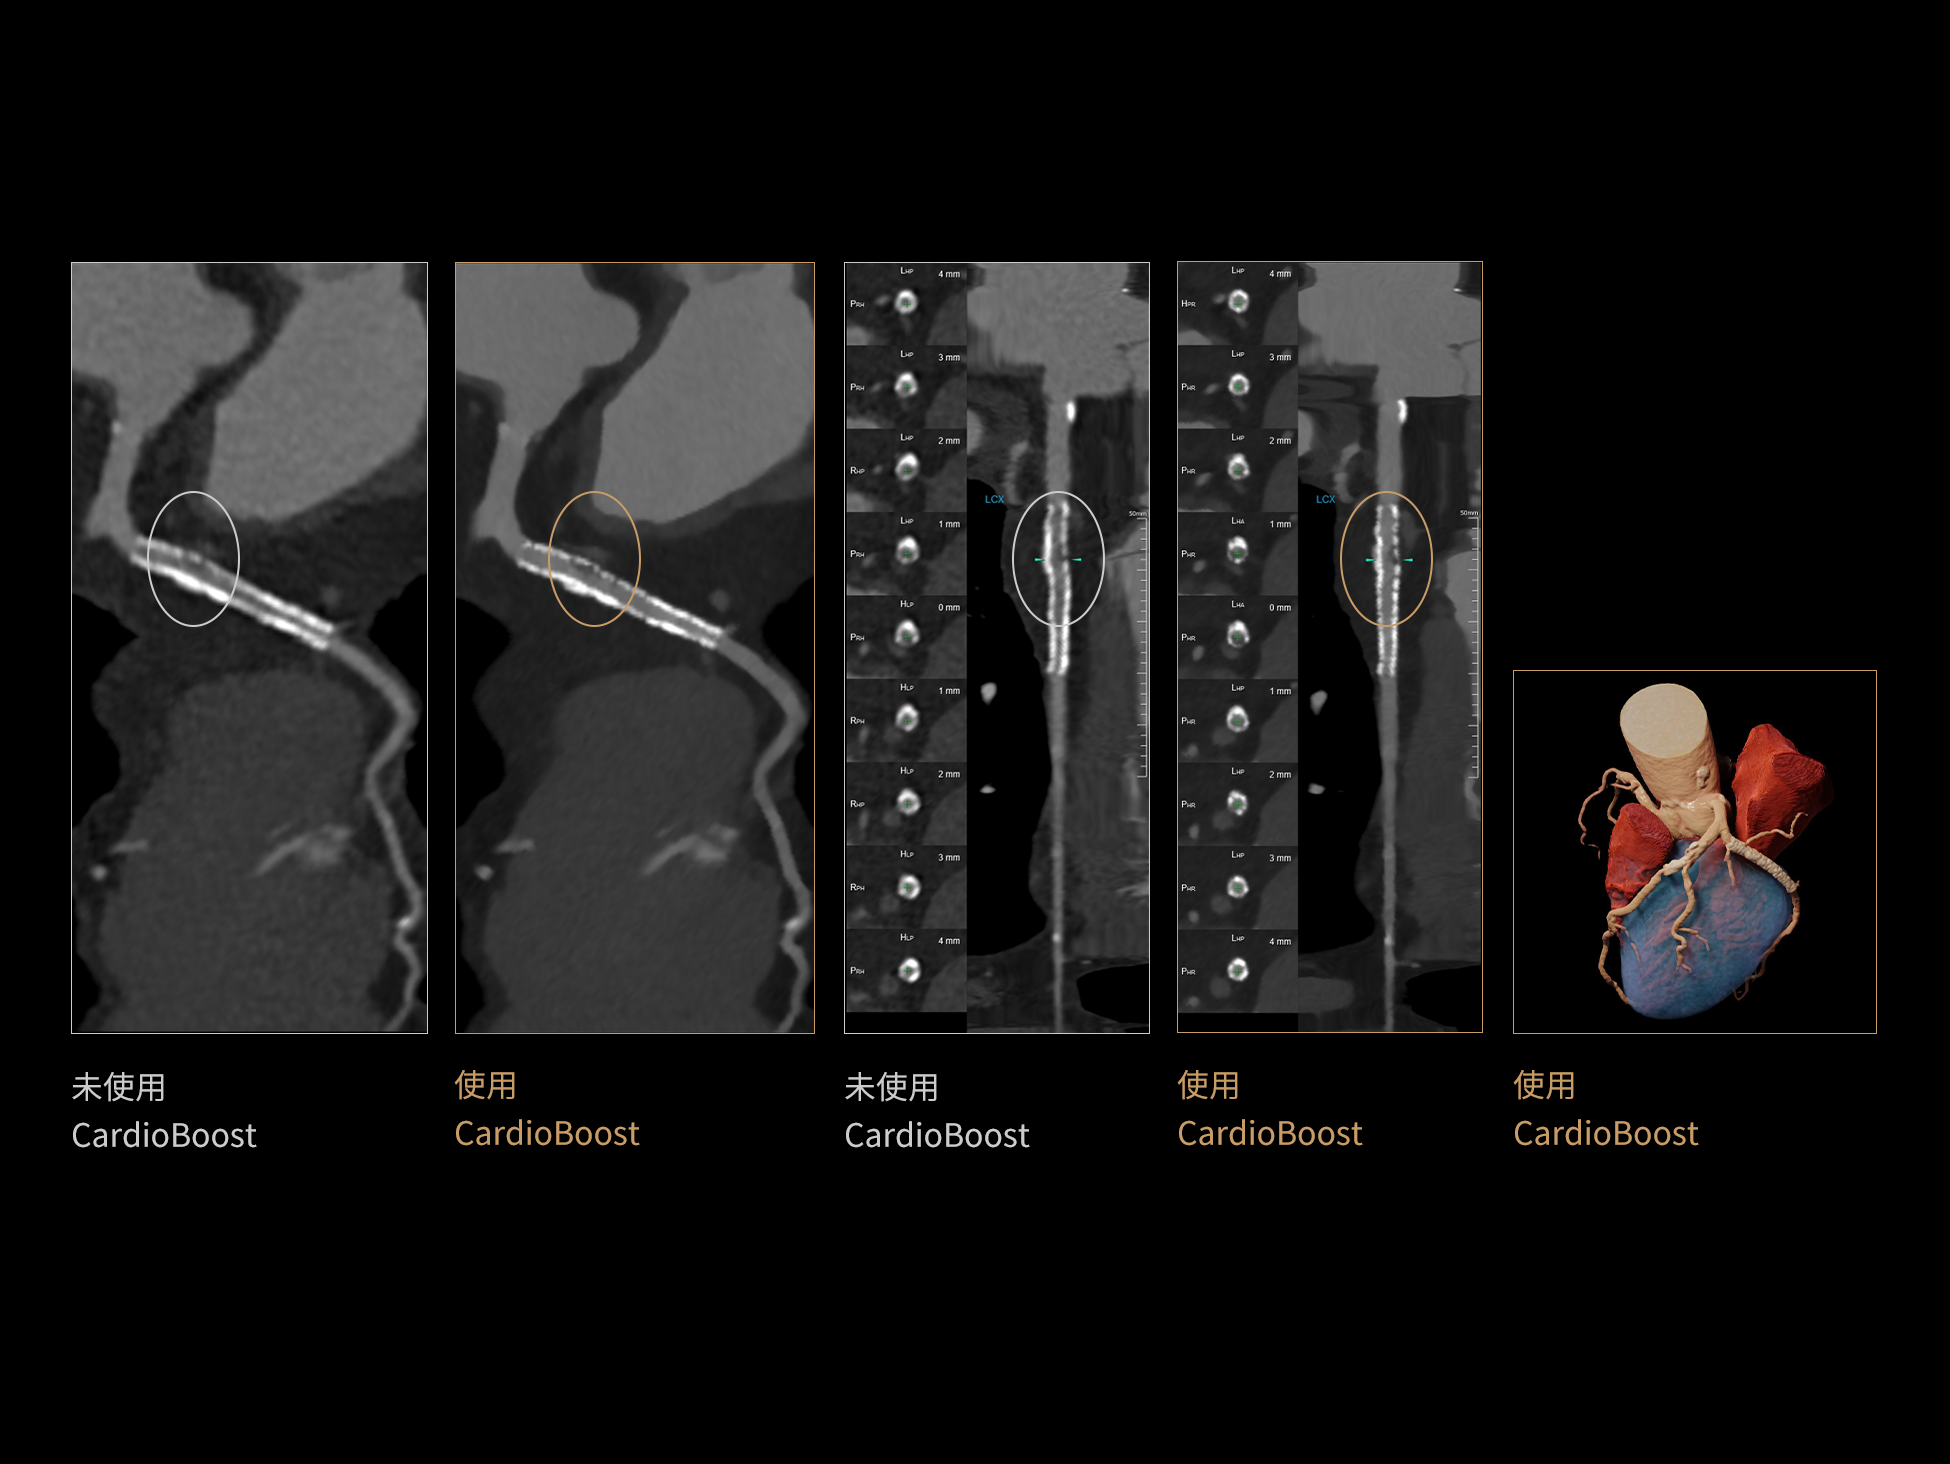

uCT 868 搭载联影最新一代 uSense 人工智能平台,将智能化深度融入 CT 扫描全流程,从感知细微生理运动到精细结构探测,再到多场景诊疗优化。以 AI 为核心驱动力,uSense 重塑成像各环节,打造高效、高清的智慧扫查体验。在心脏成像领域,uSense 结合宽体探测器、心脏专研AI重建算法与AI冠脉运动追焦技术,在保持低剂量的同时,有效抑制运动伪影,精准呈现软斑块、混合型斑块及支架细节,助力冠脉成像惠及更多患者。针对多科室疾病临床应用场景,uSense 平台提供全方位的智能解决方案:包括头部运动伪影智能校正、金属植入物伪影抑制、扫描视野扩展等先进算法。这些创新技术使 uCT 868 能够构建覆盖全场景的智能诊疗体系,持续拓展 AI 赋能医学影像的边界。